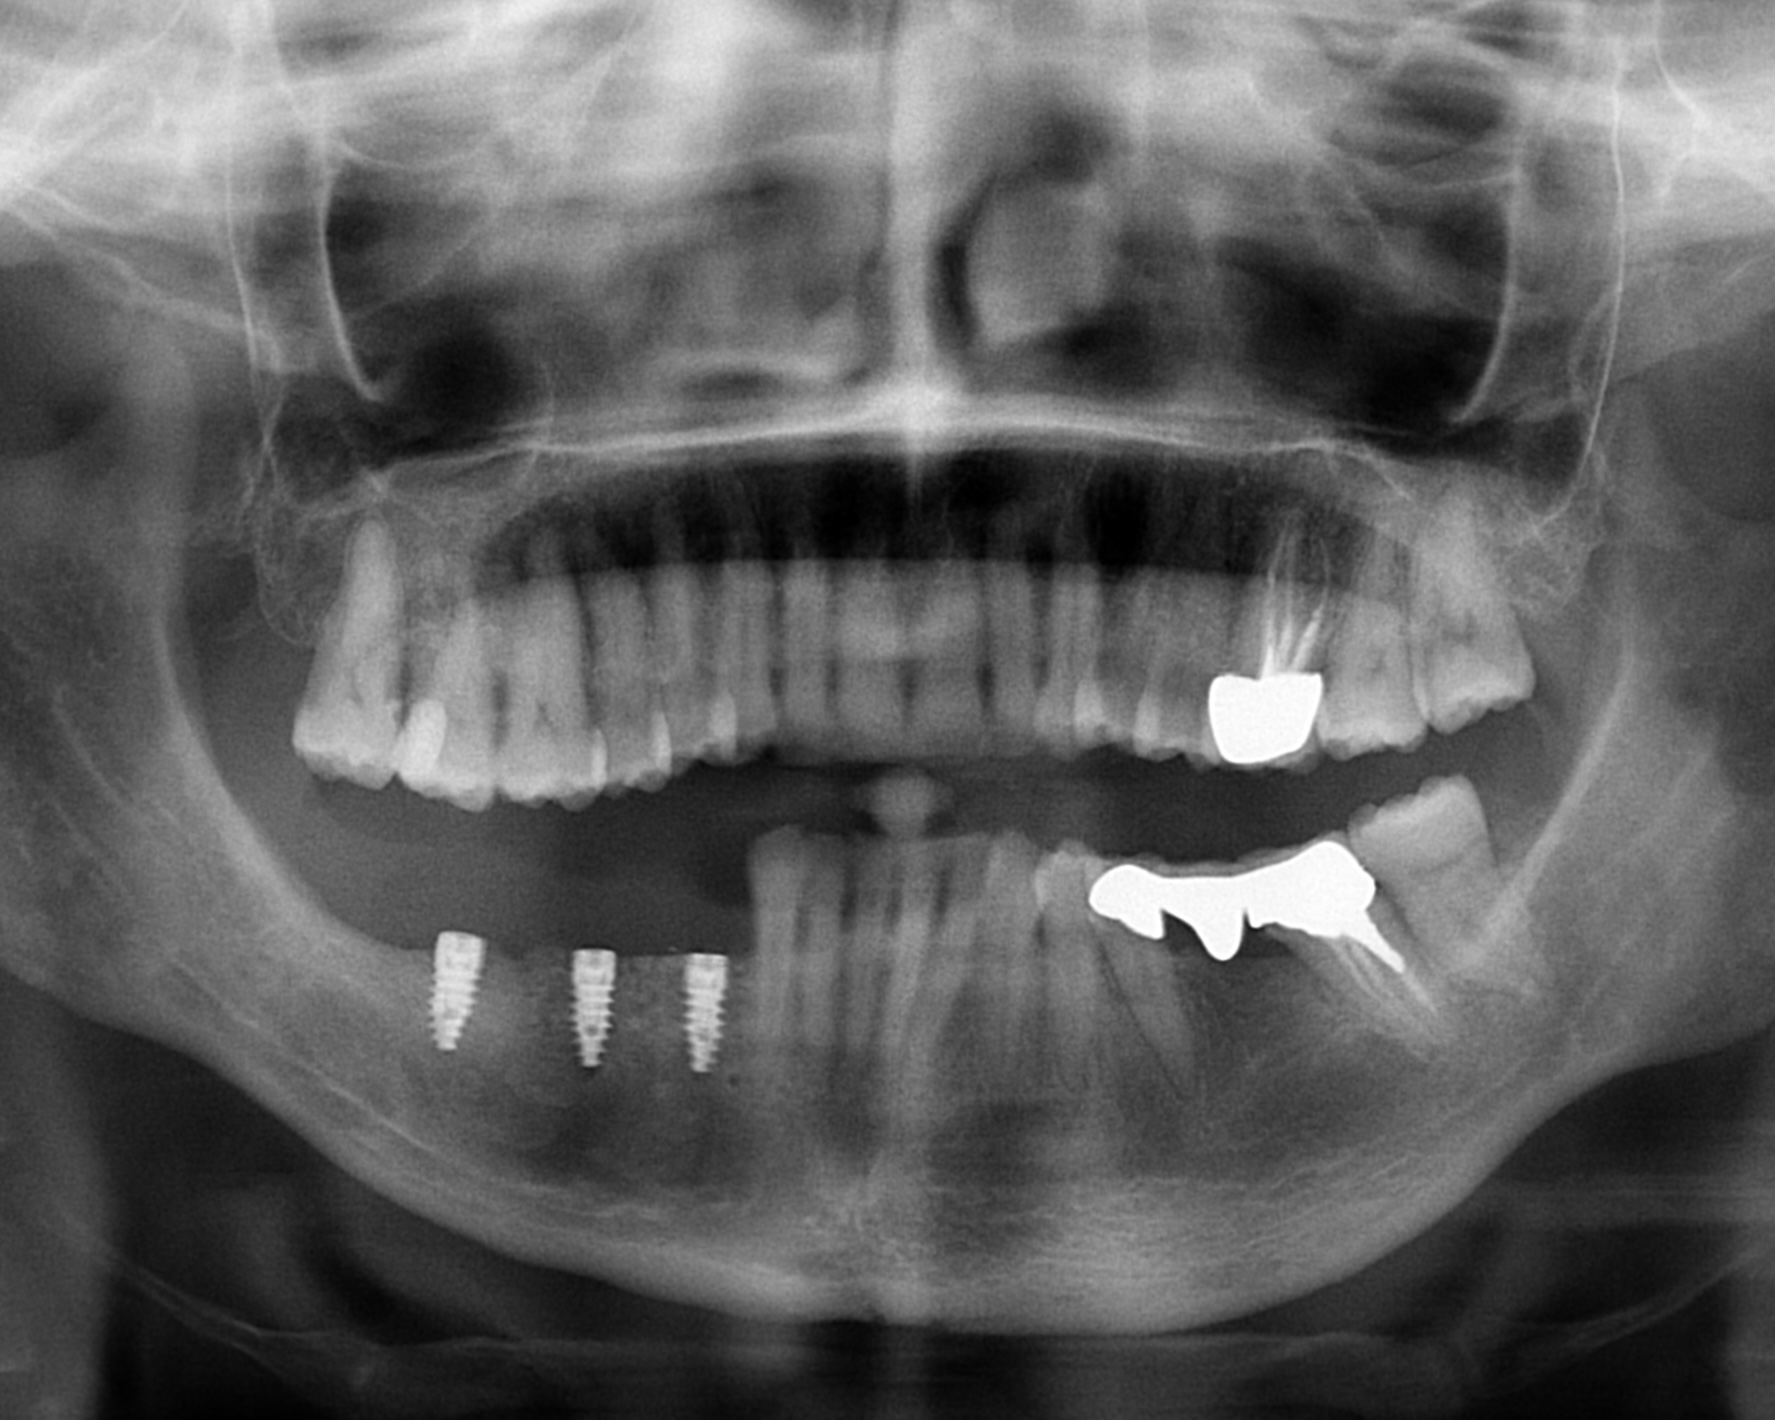

Si termina l’intervento suturando i lembi tramite punti a materassaio profondi con filo monofilamento riassorbibile 6/0, e punti staccati superficiali con filo monofilamento riassorbibile 4/0, entrambi Butterfly Flysorb Mono (Butterfly Italia srl, Cavenago di Brianza, Monza e Brianza). Viene quindi eseguita una OPT di controllo, che mostra il corretto posizionamento della griglia (Figura 8).

Al termine del posizionamento implantare si esegue il riposizionamento e la sutura dei lembi; quindi, terminato l’intervento chirurgico, si effettua una nuova OPT di controllo per confermare il corretto inserimento implantare (Figura 11).